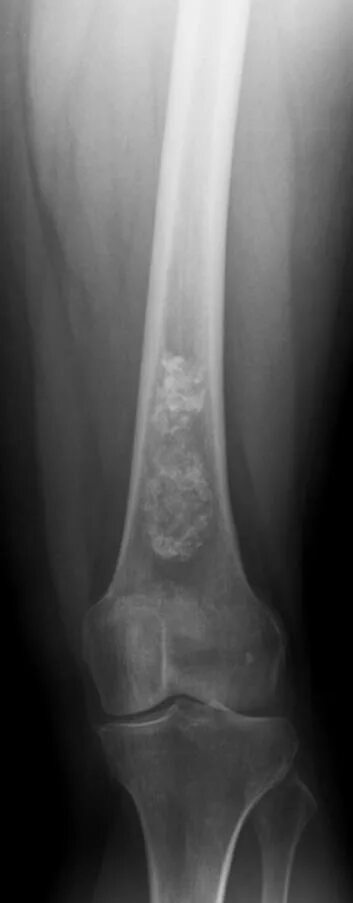

Обызвествление места прикрепления сухожилий